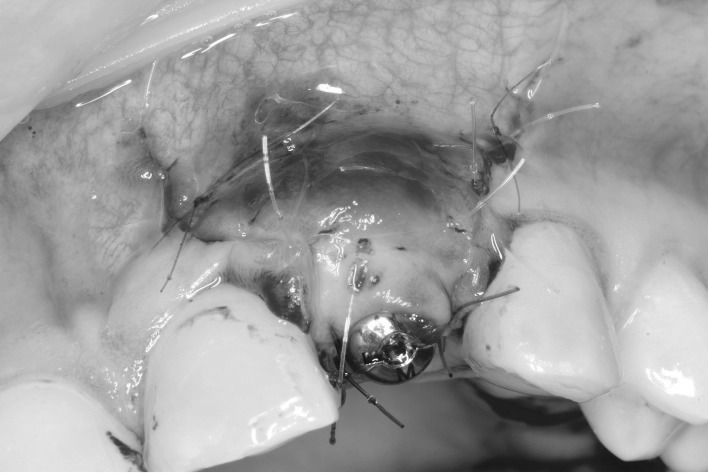

Процедуры установки имплантата и GBR прошли без осложнений; первичная стабильность имплантата составила 35 Н·см (Dentium Implantium 3.5 мм × 10 мм). GBR проводилась с использованием смеси аутогенной кости и частиц Bio-Oss® (Geistlich), а также мембраны Bio-Gide (Geistlich). Область операции была ушита швами Prolene 6/0. Во время операции не было отмечено признаков избыточного кровотечения, характерного для повреждения сосудов.

Интраоперационный вид. Имплантат установлен немедленно в области верхнего левого латерального резца после НКР и пластики мягких тканей. Заживляющий абатмент установлен, лоскуты ушиты.